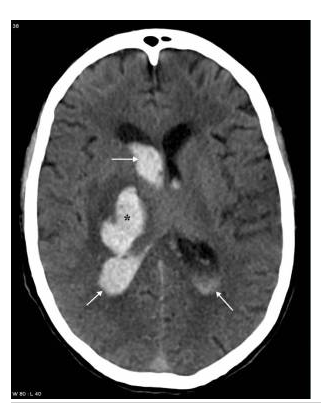

Hématome profond chez un patient âgé hypertendu en scanner.

Coupe axiale sans injection de produit de contraste iodé : hyperdensité spontanée (astérisque) de la région des noyaux gris centraux. Rupture de cet hématome dans le carrefour ventriculaire droit entraînant une hémorragie intraventriculaire avec dilatation ventriculaire (flèches). Pas d’indication à la réalisation d’explorations vasculaires complémentaires.